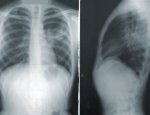

Проживающий в Цинциннати на территории штата Огайо 35-летний американец Джоуи Лайкинс нашел потерянное 5 лет назад кольцо, которое он использовал для пирсинга носа. Причём оно было обнаружено в легком. В прошлом месяце мужчину срочно доставили в приёмное отделение с подозрением на тяжелую пневмонию, так как он задыхался и очень сильно кашлял. Врачи провели сканирование, которое показало, что никакой пневмонии у Джоуи нет, но в верхней левой доли легкого явно прослеживается посторонний предмет, похожий на кольцо.

А пациент действительно подтвердил, что 5 лет назад он носил пирсинг в носу, но кольцо исчезло, и сам мужчина считал его утерянным. Оказалось, что каким-то невероятным образом оно попало внутрь его организма. Врачи прибегли к помощи бронхоскопии и удалили инородный предмет. При этой процедуре трубку вводят через горло в лёгкие, она также применяется и для исследования этих органов.